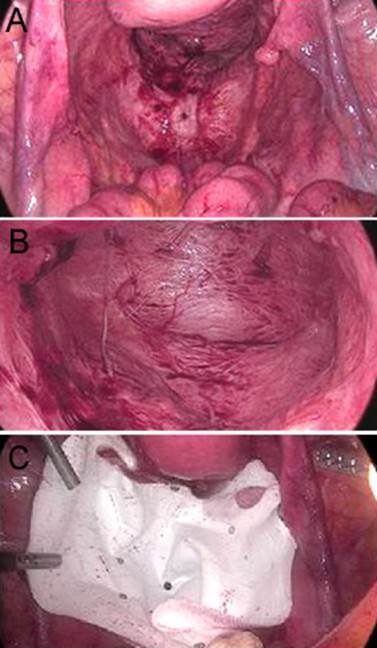

Figura 6. Caso 2: Reparación de la hernia por abordaje abdominal laparoscópico. A y B. Imagen intrabdominal de la hernia. C. Colocación de la malla.

Mujer de 58 años, sin antecedentes de relevancia, sometida a una operación de Miles asistida por videolaparoscopia con cierre primario del periné por adenocarcinoma del recto inferior, consultó al 4º mes postoperatorio con bulto perineal de crecimiento progresivo, disuria y molestia local. Se diagnosticó HP reductible e incoercible (Figs. 4 y 5) Se reparó por abordaje abdominal videolaparoscópico. Luego de liberar escasas adherencias laxas se redujo el contenido hacia la cavidad abdominal procediendo a la reparación del piso pelviano con prótesis de doble revestimiento, fijada a los reparos óseos y músculos del piso pelviano con dispositivo de fijación, sin omentoplastia (Fig. 6). Con buena evolución postoperatoria se otorgó alta institucional al 2º día postoperatorio. A los 12 meses de la cirugía continúa sin recidiva de la hernia (Fig. 7).